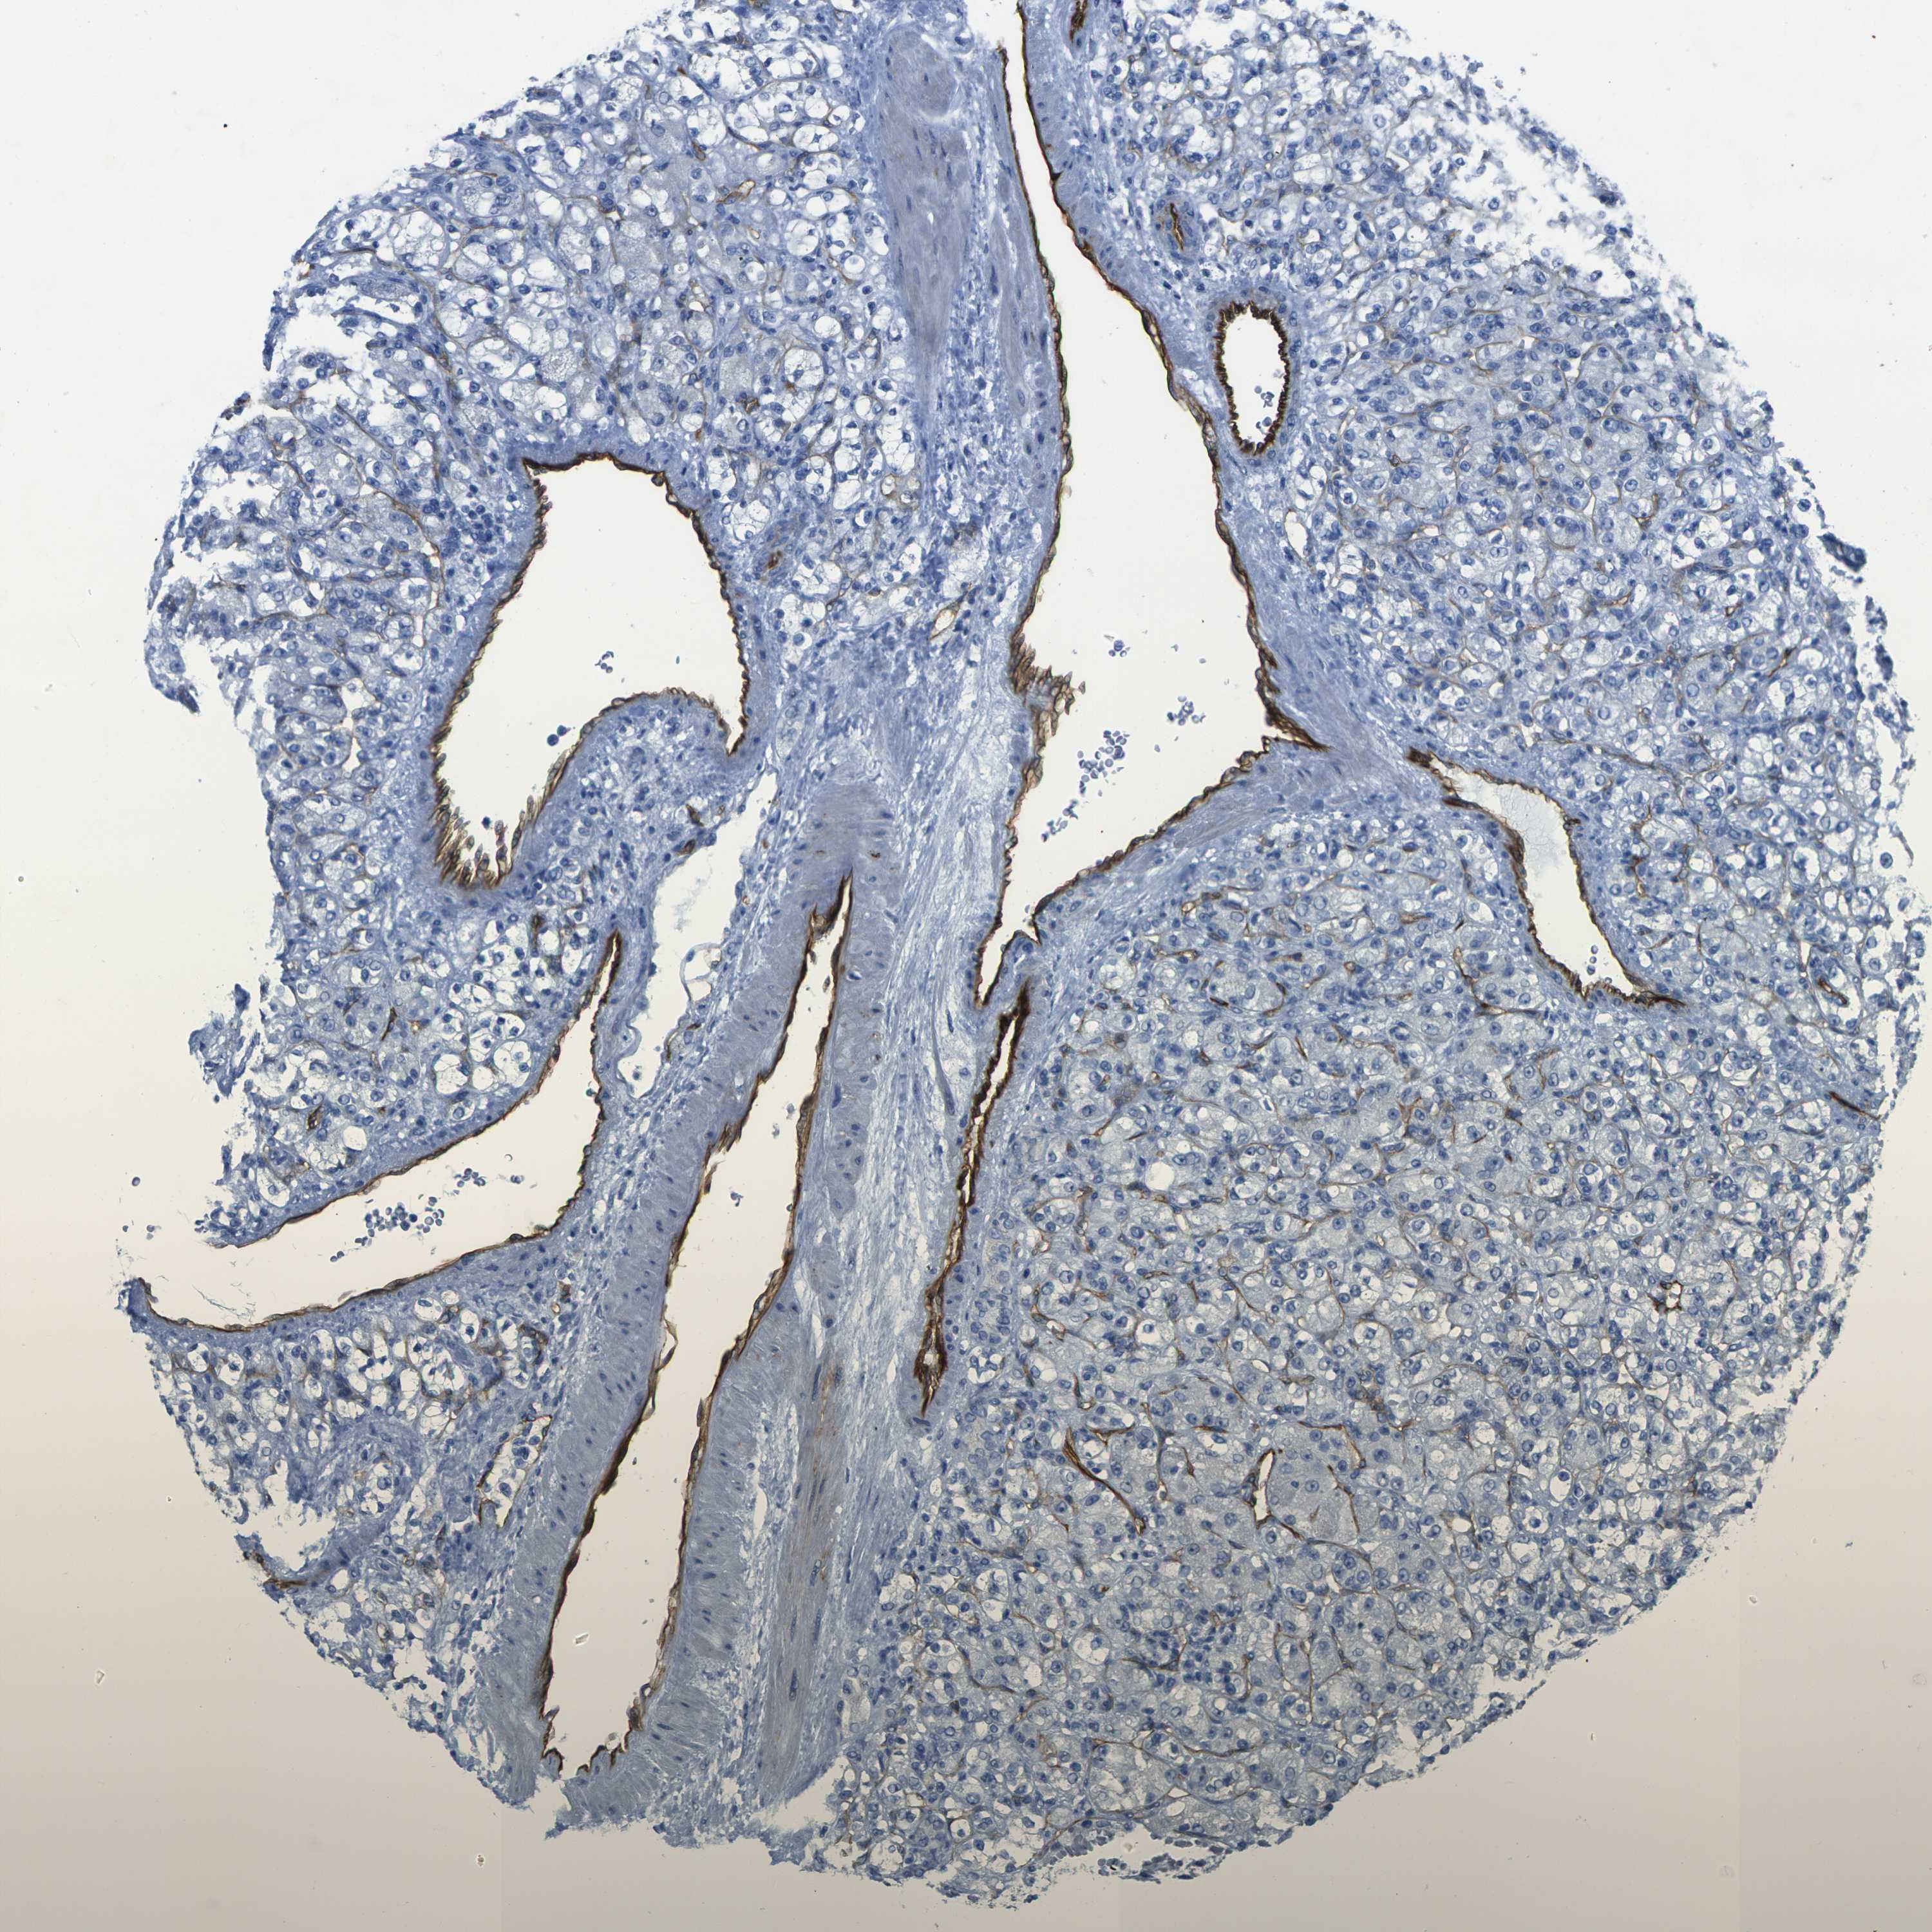

HSPA12B is validated prognostic, high expression is favorable in Kidney Renal Clear Cell Carcinoma (TCGA)

Best expression cut offi

Based on the FPKM value of each gene, patients were classified into two groups and association between prognosis (survival) and gene expression (FPKM) was examined. The best expression cut-off refers the FPKM value that yields maximal difference with regard to survival between the two groups at the lowest log-rank P-value. Best expression cut-off was selected based on survival analysis .

When clicking on this number, the vertical dashed line indicating cut-off, the interactive survival plot, and the Kaplan-Meier curve will be adjusted to show results based on the best expression cut-off.

: 3.4

TCGA RNA samplesi

RNA-seq data is reported as average FPKM (number Fragments Per Kilobase of exon per Million reads), generated by the The Cancer Genome Atlas (TCGA) .

Normal distribution across the dataset is visualized with box plots, shown as median and 25th and 75th percentiles. Points are displayed as outliers if they are above or below 1.5 times the interquartile range. FPKM values of the individual samples are presented next to the box plot.

Average pTPM 7.5

Number of samples 521